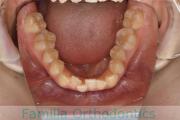

上顎

下顎